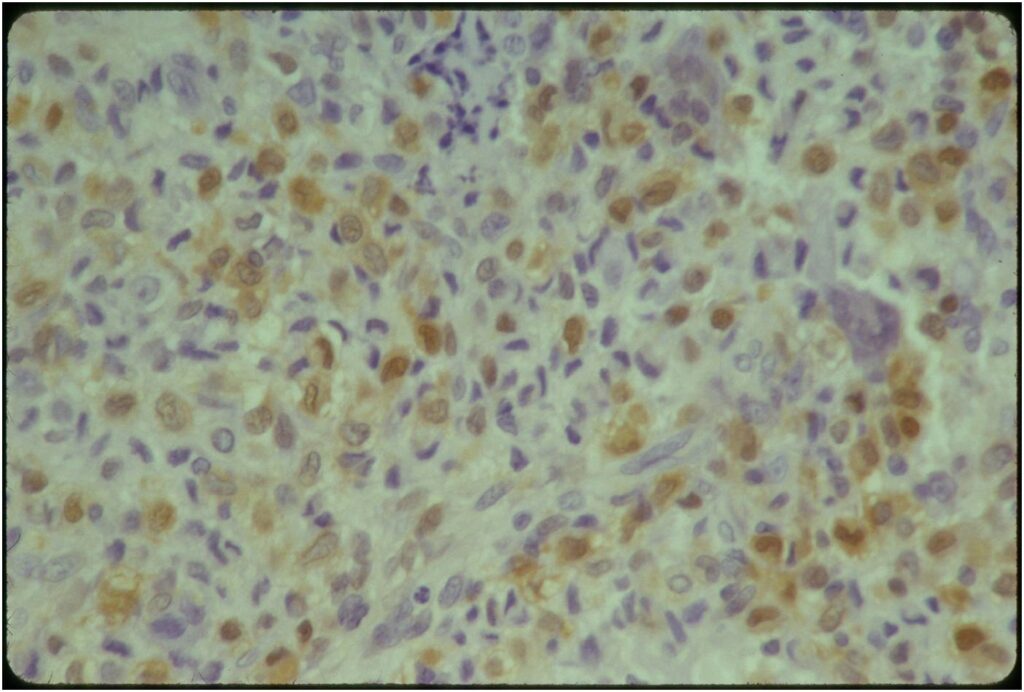

Microscopic Pathology

- Variable appearance depending on percentage of cells, necrosis, cartilage matrix formation and ABC change

- The tumor is composed of chondroblasts that have a distinct, thick cell membrane. The thick cell membrane gives it a “Chicken Wire Fence Appearance,” especially when the cell membranes are calcified